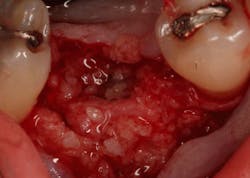

Excellent interseptal bone width was present, both buccal and lingual plates were present, and an adequate amount of bone was present coronal to the inferior alveolar nerve to allow for immediate implant placement. A sulcular incision was made around K and the adjacent teeth, and a full-thickness buccal and lingual flap was reflected. The tooth was sectioned in half, and the mesial and distal roots were elevated. The socket was degranulated with a round diamond bur and copiously irrigated with chlorhexidine gluconate 0.12% rinse. An osteotomy was completed in the interseptal area, and a bone-level 4.8- x 10-mm implant was placed to 35 Ncm. A mixture of cancellous and cortical allograft was infused with autogenous plasma-rich growth factor (PRGF), which was isolated during a preprocedural blood draw. The mixture was packed into the residual socket, slightly coronal to the implant platform to account for predictable resorption during healing. (13)

A 15- x 20-mm Ossix Plus membrane was hydrated in sterile saline for three minutes and trimmed to extend roughly 3 mm beyond the buccal and lingual extent of the bone graft and roughly 1 mm from the adjacent teeth. A sterile template is included in each membrane package; it can be trimmed to the appropriate dimensions and superimposed on the Ossix Plus membrane for final trimming to ensure the exact dimensions desired are obtained. This membrane can also be sutured, if necessary. When this technique is used, it is important to pass the suture needle through the membrane at a 90-degree angle to avoid tearing the membrane.

In this case, I placed an autogenous fibrin clot, which was isolated from the fractionated blood draw, over the Ossix Plus membrane and sutured, without obtaining primary closure, using a CV-5 Gore-Tex (W.L. Gore & Associates Inc.). This technique is designed to help facilitate the formation of a blood clot over the Ossix Plus membrane. It can be used with the addition of a collagen plug over the membrane, or you can just suture and allow a natural clot to form.